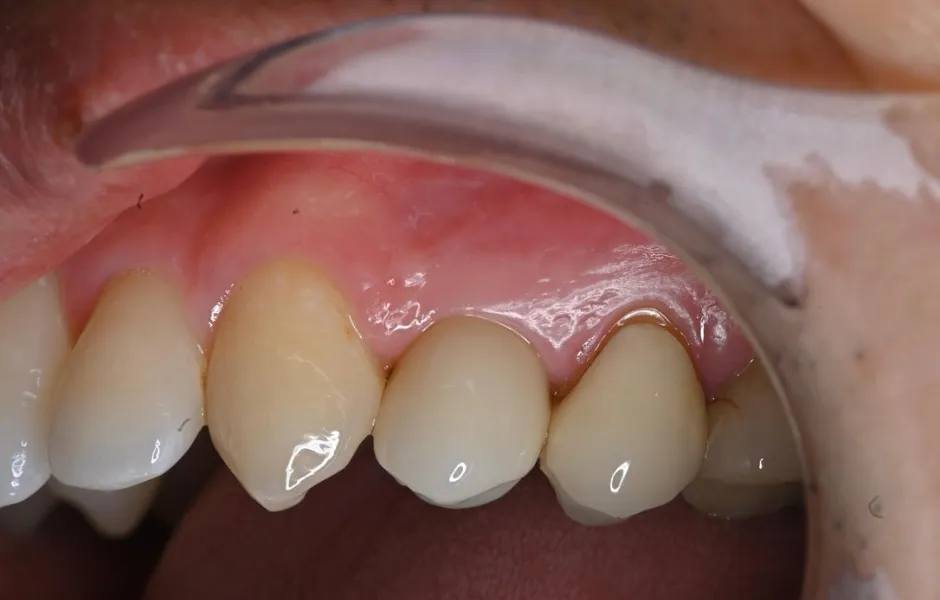

歯周病治療

歯磨きが不充分だと歯肉が炎症を起こし、放置していると歯が抜けてしまいます。医院でのプロによるクリーニングと日々の歯磨きで清潔な状態を保ち、健康を維持します。

歯周病治療 -